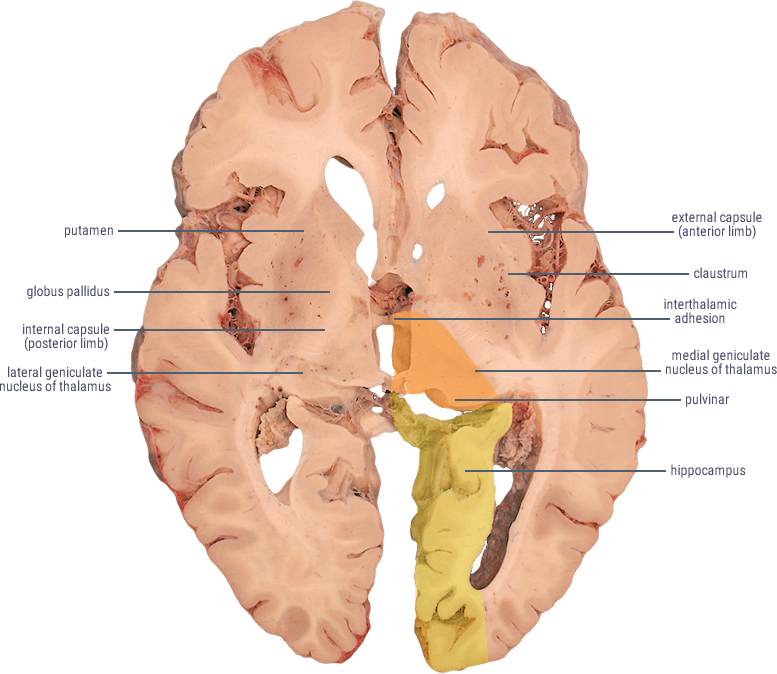

from ditki.com

Neuroanatomy Glossary Posterior Cerebral Artery (PCA) Stroke ditki

Neuroanatomy Glossary Posterior Cerebral Artery (PCA) Stroke ditki What Is A Pca Stroke Posterior cerebral artery (pca) infarcts arise, as the name says, from occlusion of the posterior cerebral artery. Posterior circulation ischaemic stroke is a clinical syndrome associated with ischaemia related to stenosis, in situ thrombosis,. This article provides an overview of pca stroke and focuses exclusively on stroke of arterial origin involving the pca territory (see the images below). A solid. What Is A Pca Stroke.

Neuroanatomy Glossary Posterior Cerebral Artery (PCA) Stroke ditki What Is A Pca Stroke Posterior circulation ischaemic stroke is a clinical syndrome associated with ischaemia related to stenosis, in situ thrombosis,. Posterior cerebral artery (pca) stroke is a type of ischemic stroke that occurs when there is a blockage or reduced blood flow in the posterior. It is a type of posterior circulation. A solid understanding of the pathophysiology of a posterior cerebral artery. What Is A Pca Stroke.